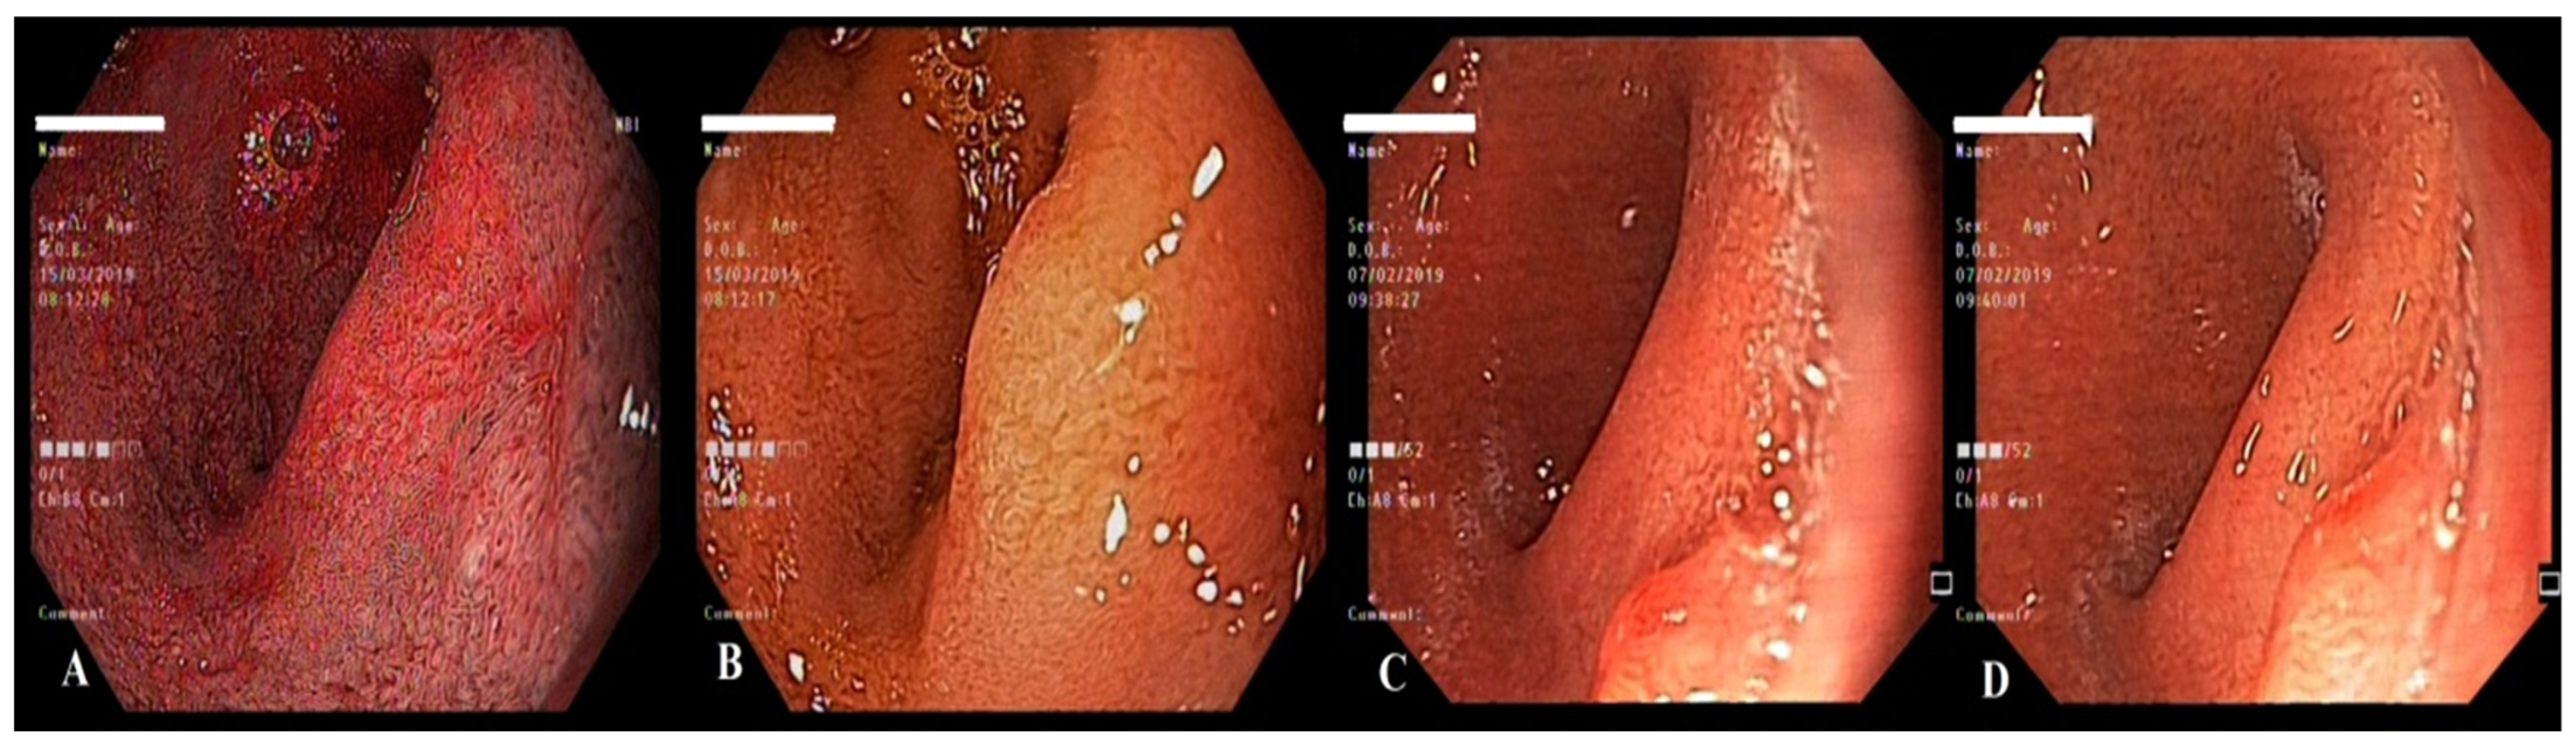

2. Case Report 1

3. Case Report 2